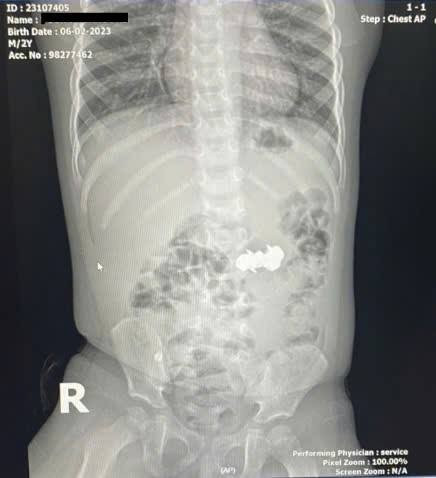

Ngay sau khi xác định nguyên nhân, ê-kíp bác sĩ khoa Thăm dò chức năng phối hợp với khoa Gây mê Hồi sức đã nhanh chóng tiến hành nội soi cấp cứu gắp dị vật. Quá trình can thiệp được thực hiện hết sức thận trọng nhằm tránh gây tổn thương cho thực quản và dạ dày. Sau hơn một giờ đồng hồ, toàn bộ bốn viên đinh nam châm được lấy ra an toàn. Sau thủ thuật, sức khỏe của bệnh nhi ổn định, tỉnh táo, ăn uống được và đã xuất viện sau thời gian theo dõi ngắn hạn.